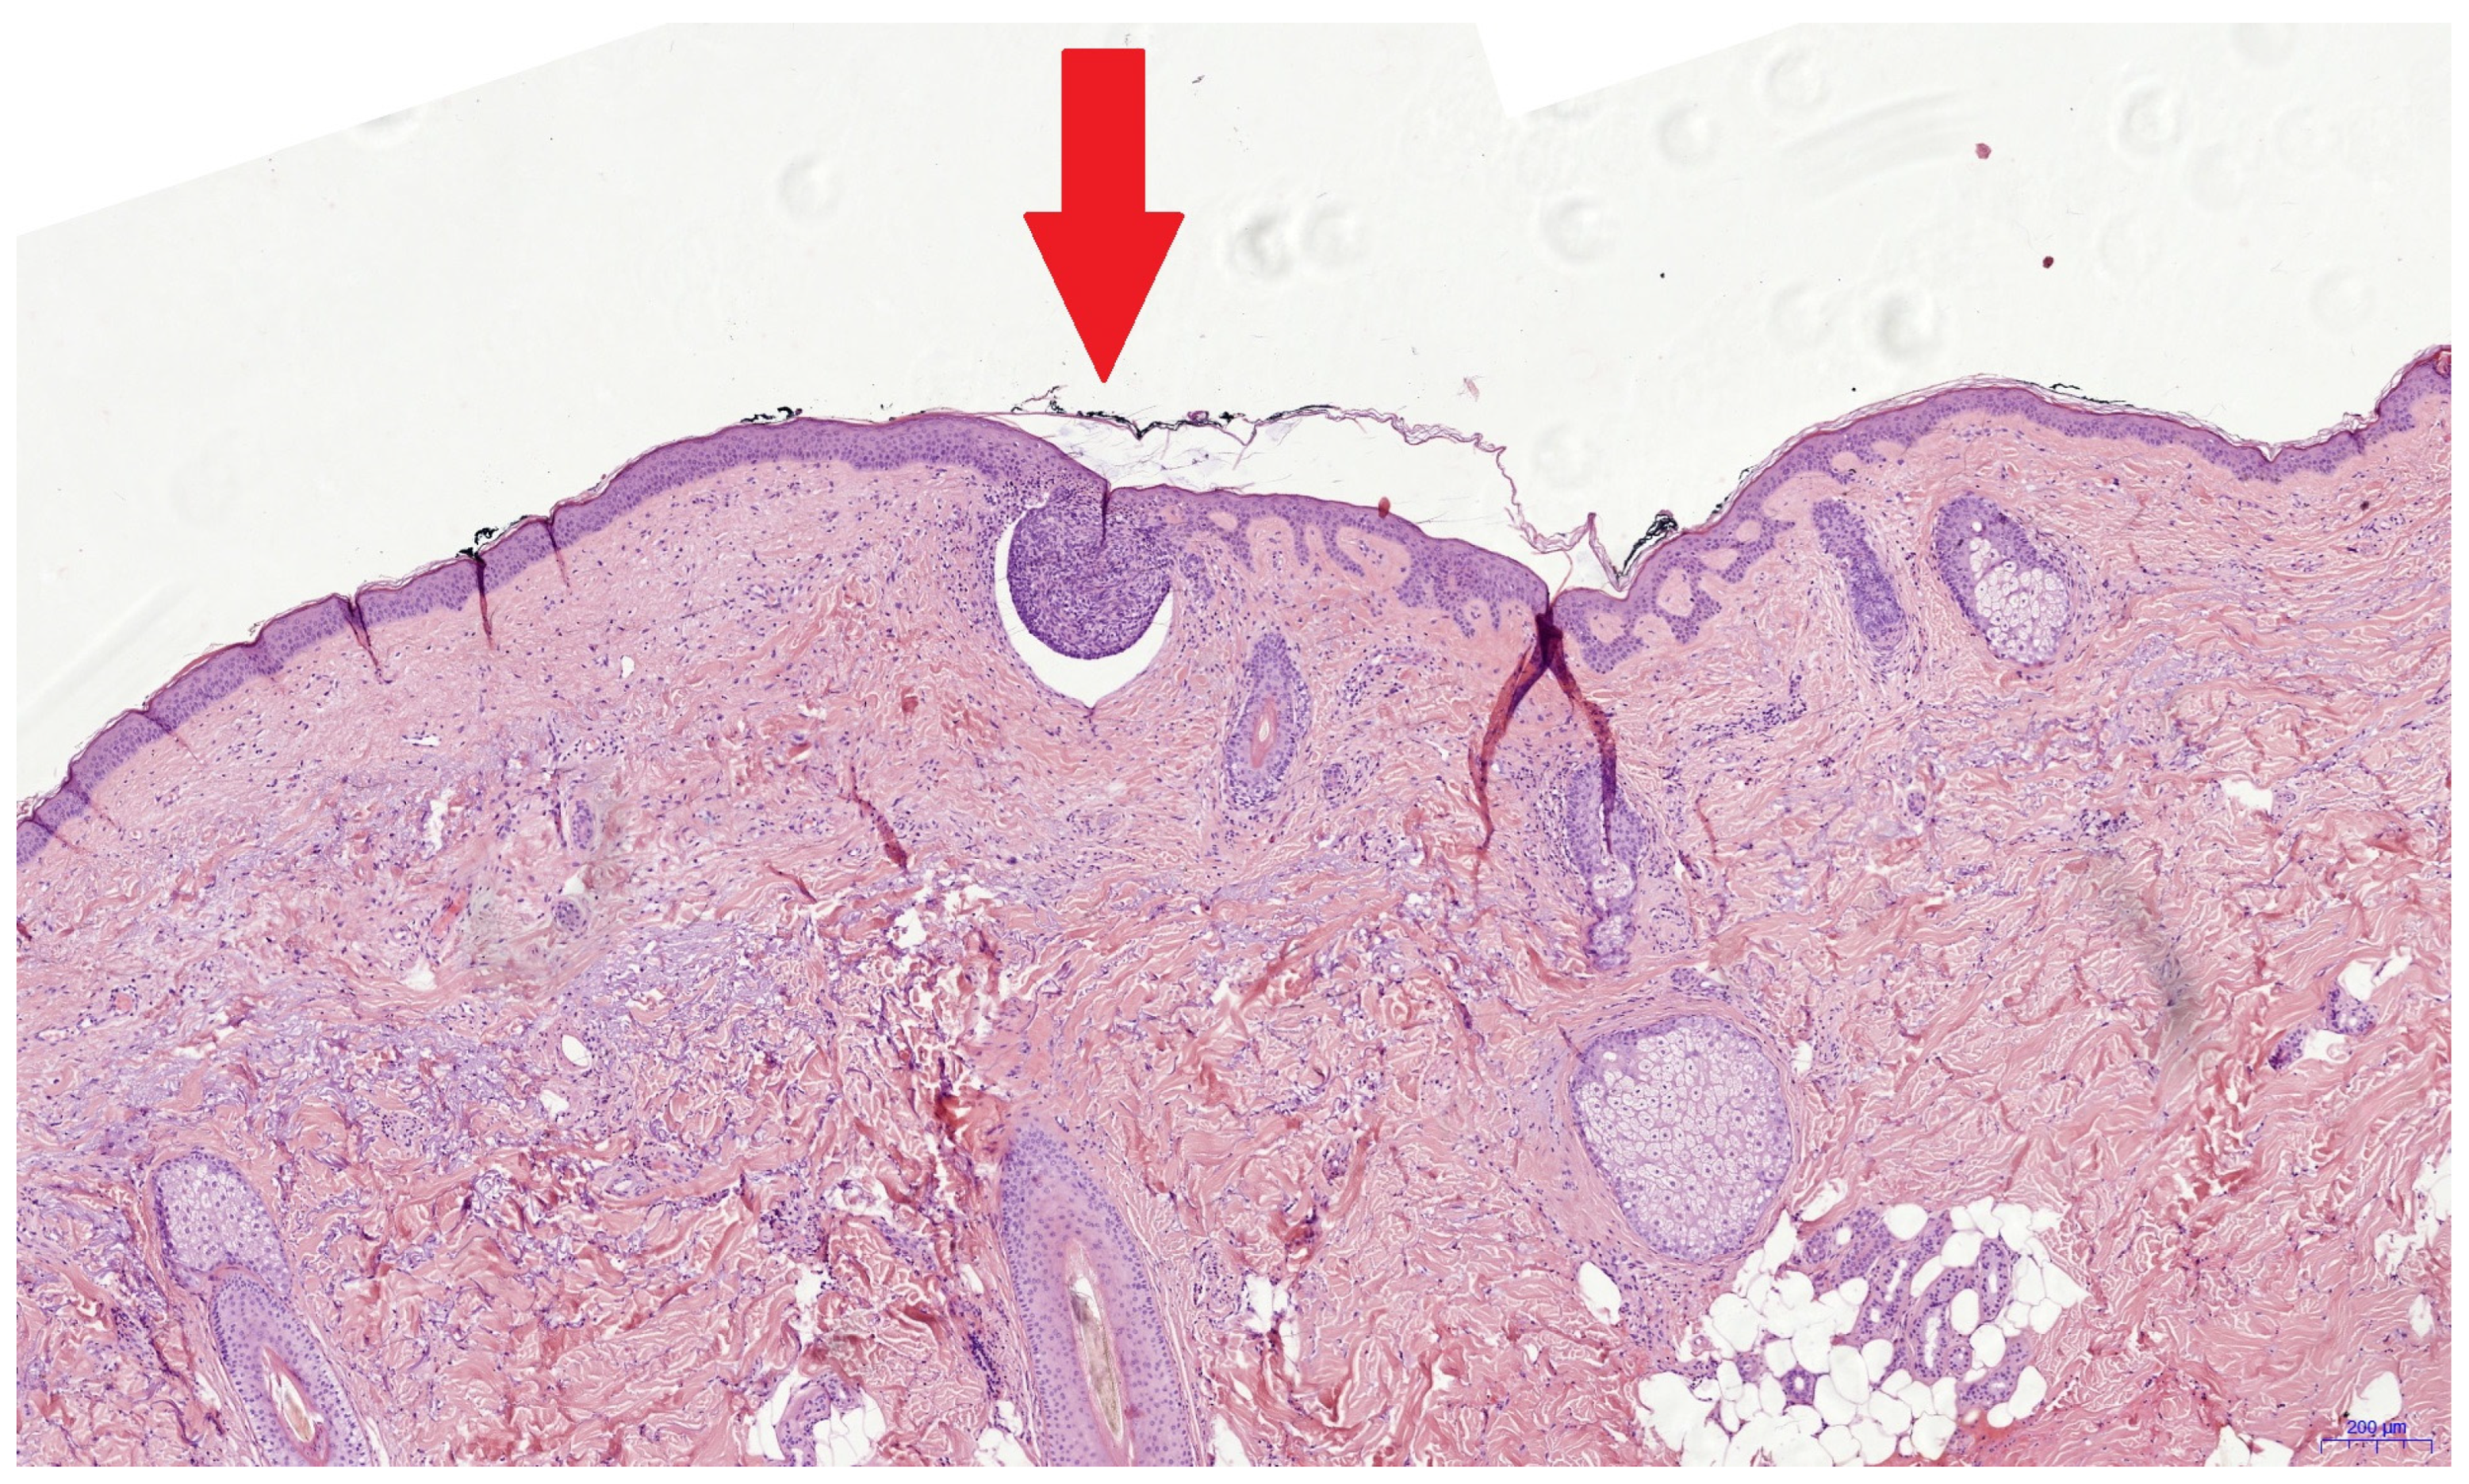

It was reported that investigators only needed a two-day introduction to confidently use the evRCM device [28]. Safe evRCM assessment might require more time for cutaneous surgeons due to their limited histologic experience. The low rate of positive surgical margins (n = 10) is a limiting factor of this study. In contrast to previous studies, we only analyzed re-excisions following an incomplete primary excision. Accordingly, only a small tumor residue could be expected in the surgical margins, making assessment more difficult. During the pathology processing, the re-excised tissue is placed on the outer edge, cast in paraffin, and sectioned from the outside until a continuous tissue section completely covered by the epidermis can be produced, losing the outer edges in the process. Histological assessment is performed on a section from the inside of the re-excised specimen. Therefore, an incomplete excision may be found in the pathological assessment even though the tumor was completely removed (Figure 2). After the pathologist’s retrospective assessment of the pathological and evRCM findings and a further assessment of the medical history, this situation was possible in four of eight cases and probable in two. Only one false negative incomplete excision could be confirmed retrospectively by the pathologist using the evRCM images. The tumor could be histologically confirmed in two cases in a later re-excision. Consequently, how many of the ten cases were completely removed remains unclear, so the sensitivity can range between 0.2 and 0.8.

Figure 2. This histological image shows a superficial BCC nest with a diameter of 0.3 mm (red arrow). It is possible that such tumor remnants are not present in the true surgical margin and cannot be seen using evRCM. The histological findings might be false positive due to sectioning of the re-excised specimen.